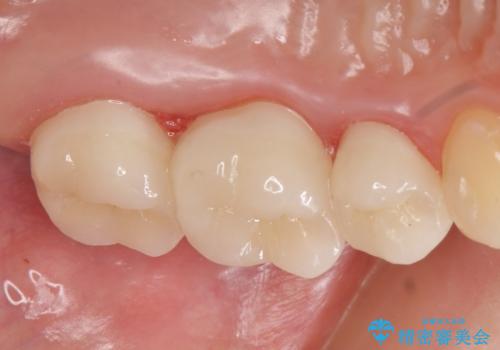

- 他院にて左上5番目の歯の根管治療を行っていたが、痛みが引かないため当院にいらっしゃった方の症例です。

左上5は再根管治療を行い症状の緩解を確認後、オールセラミッククラウンによる補綴を行いました。

左上6、7番目の歯もしみるとのことだったので古い樹脂及び虫歯を除去後、オールセラミッククラウンによる補綴を行いました。

今回用いたオールセラミッククラウンはジルコニアフレームという白い素材の上にセラミックを盛っているため、審美性が非常に高いのが特徴です。

また、ジルコニアは人工ダイヤモンドの材料にも使われているほど高い強度を持っており、そのためオールセラミッククラウンは審美性だけでなく、奥歯やブリッジの補綴も可能とするクラウンです。